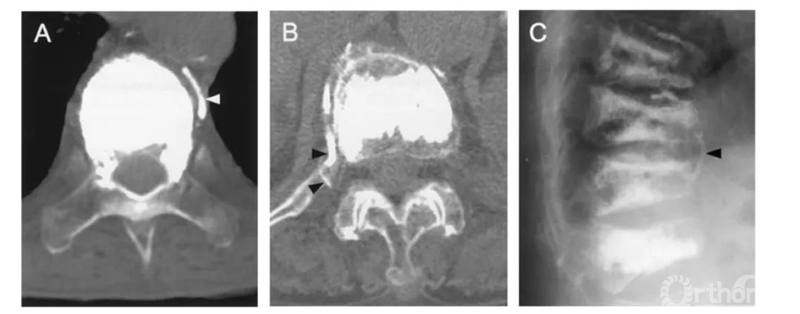

该患者做完PVP术后失血性休克症状。复查CT发现巨大的腹膜后血肿。血管造影发现L2左侧节段动脉远端破裂,行栓塞修复。

三维CT显示椎旁节段动脉就在椎体旁正中走行,所以椎弓根外侧穿刺安全边界在椎弓根中线以上。

比如这例,侧位X片看骨水泥在椎弓根里,可CT一扫发现已经渗漏进入椎管。

侧位X片看骨水泥在椎体里,CT显示渗漏进入椎管。

侧位X片看骨水泥在椎间孔周缘,CT显示渗漏进入椎管,累及椎间孔。